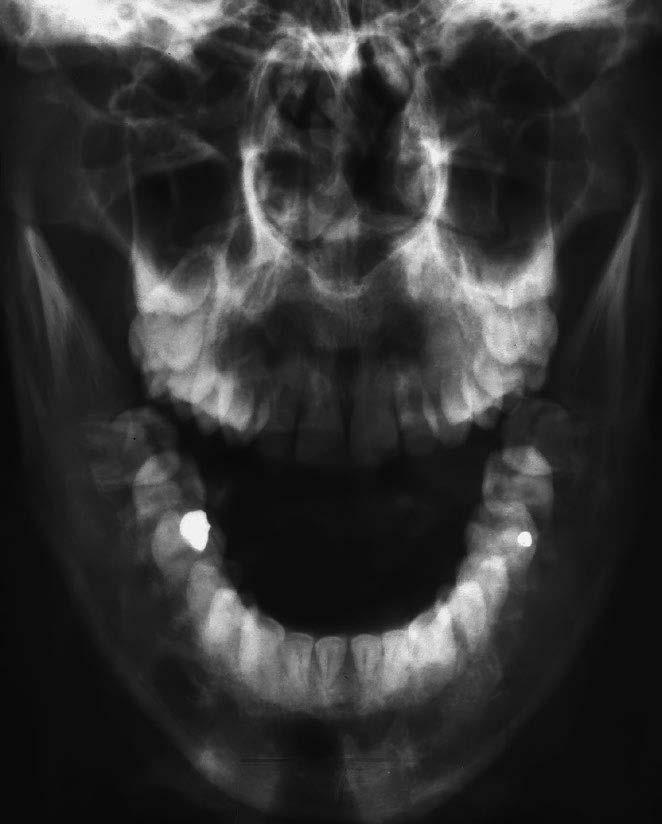

1 articulatio temporomandibularis (čelistní kloub)

2 caput mandibulae (hlavice dolní čelisti)

3 processus coronoideus (krkavčitý výběžek)

4 alveolární okraj

5 foramen mandibulae

6 protuberantia mentalis (bradový výběžek)

7 cavitas dentis (pulparis) (dřeňová dutina zubu)

8 canalis radicis dentis (zubní kanálek)

9 foramen apicis radicis dentalis

10 foramen mentale

11 canalis mandibulae (kanál v dolní čelisti)

12 angulus mandibulae (úhel dolní čelisti)

1 stříška kloubní jamky čelistního kloubu

2 articulatio temporomandibularis (čelistní kloub)

3 caput mandibulae (hlavice dolní čelisti)

4 sinus maxillaris (dutina horní čelisti)

5 cavitas nasi (nosní dutina)

6 processus coronoideus (krkavčitý výběžek)

7 maxilla (horní čelist)

8 ramus mandibulae (rameno dolní čelisti)

9 angulus mandibulae (úhel dolní čelisti)

10 dentes molares (stoličky)

12 dentes premolares (premoláry)

13 dens caninus (špičák)

14 dentes incisivi (řezáky)

15 foramen mentale

16 tuberculum mentale (sumace s projasněním trachey)

19 canalis radicis dentis (kořenový kanál)

20 cavitas dentis (pulparis) (dřeňová dutina zubu)

21 dentin korunky (zubovina)

22 sklovina 23 foramen mentale

24 radix dentis (zubní kořen)

25 dentes incisivi (řezáky)

26 dens caninus (špičák)

27 dentes premolares (premoláry)

28 dentes molares (stoličky)

10 recessus alveolaris (dno dutiny horní čelisti) 11 sinus maxillaris (dutina horní čelisti) 12 fossa pterygopalatina 13 processus pterygoideus (křídlový výběžek kosti klínové) 14 angulus mandibulae (úhel dolní čelisti) 15 stín jazyka 16 canalis mandibulae (kanál v dolní čelisti) 17 os hyoideum (jazylka) 18 foramen apicis radicis dentis